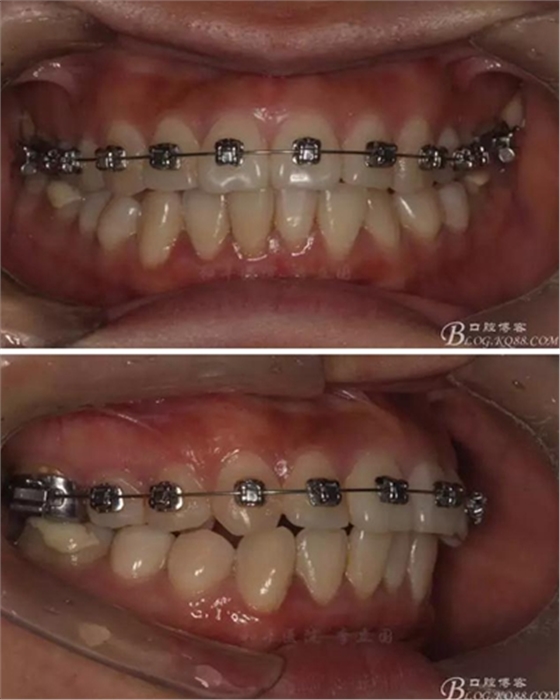

該病例主要為17、27頰側(cè)位同時伴有伸長,當(dāng)然種植支抗可以解決,但還有簡單實(shí)用的辦法嗎?如圖,在橫腭桿遠(yuǎn)中延伸出牽引鉤,位置盡量遠(yuǎn)離合平面,7粘舌側(cè)扣,牽引力的方向?yàn)閴旱图吧嘞?,下圖為兩個月的效果,17已到位,27還未到位。